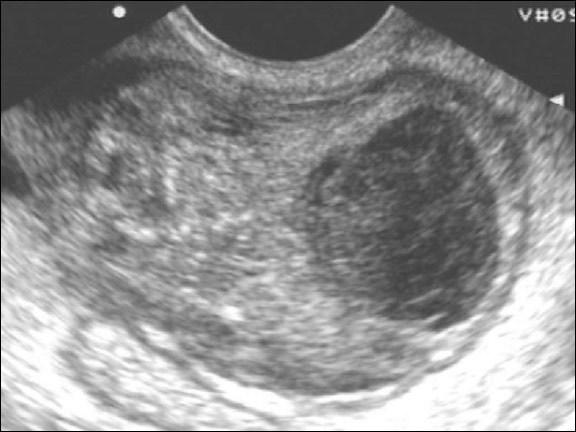

По данным гинекологического УЗИ пиовар визуализируется в виде эхопозитивного округлого образования с неоднородным внутренним содержимым из-за множественных включений, неравномерно утолщенной капсулой (6-10 мм).